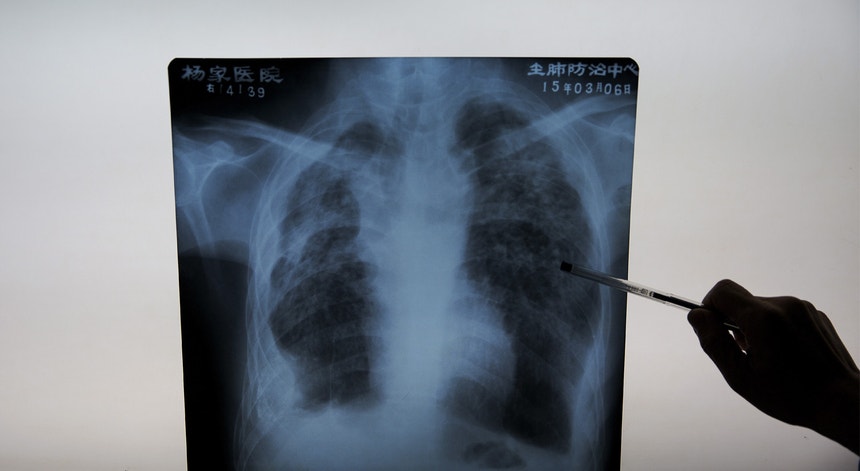

Cancro no pulmão: novos tratamentos dão mais esperança aos doentes

Os novos tratamentos para o cancro do pulmão estão a permitir duplicar o tempo de sobrevivência dos doentes. Mas a maioria dos casos ainda tem de passar pela quimioterapia.

O tabaco continua a ser um dos principais responsáveis pelo cancro do pulmão